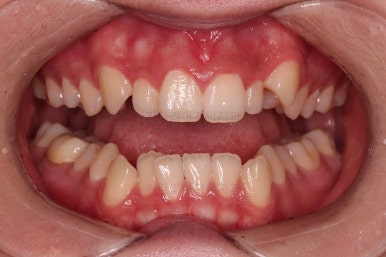

마찬가지로 초진 시 입안의 모습인데요.

위아래 앞니가 삐뚤고, 송곳니는 덧니처럼 불룩 튀어나가 있네요.

위아래 앞니는 안으로 굽어 들어와 있는 옥니(뻐드렁니 반대) 양상이었고요.

그리고 마무리 때 디테일에 문제가 생길 수 있는 부분인데, 윗니 대문니(가장 중간 치아)와 송곳니 사이의 치아를 작은 앞니라고 하는데요.

이 작은 앞니가 가져야 될 크기보다 더 작은 양상이었습니다.

이런 치아를 왜소치라교 표현합니다.